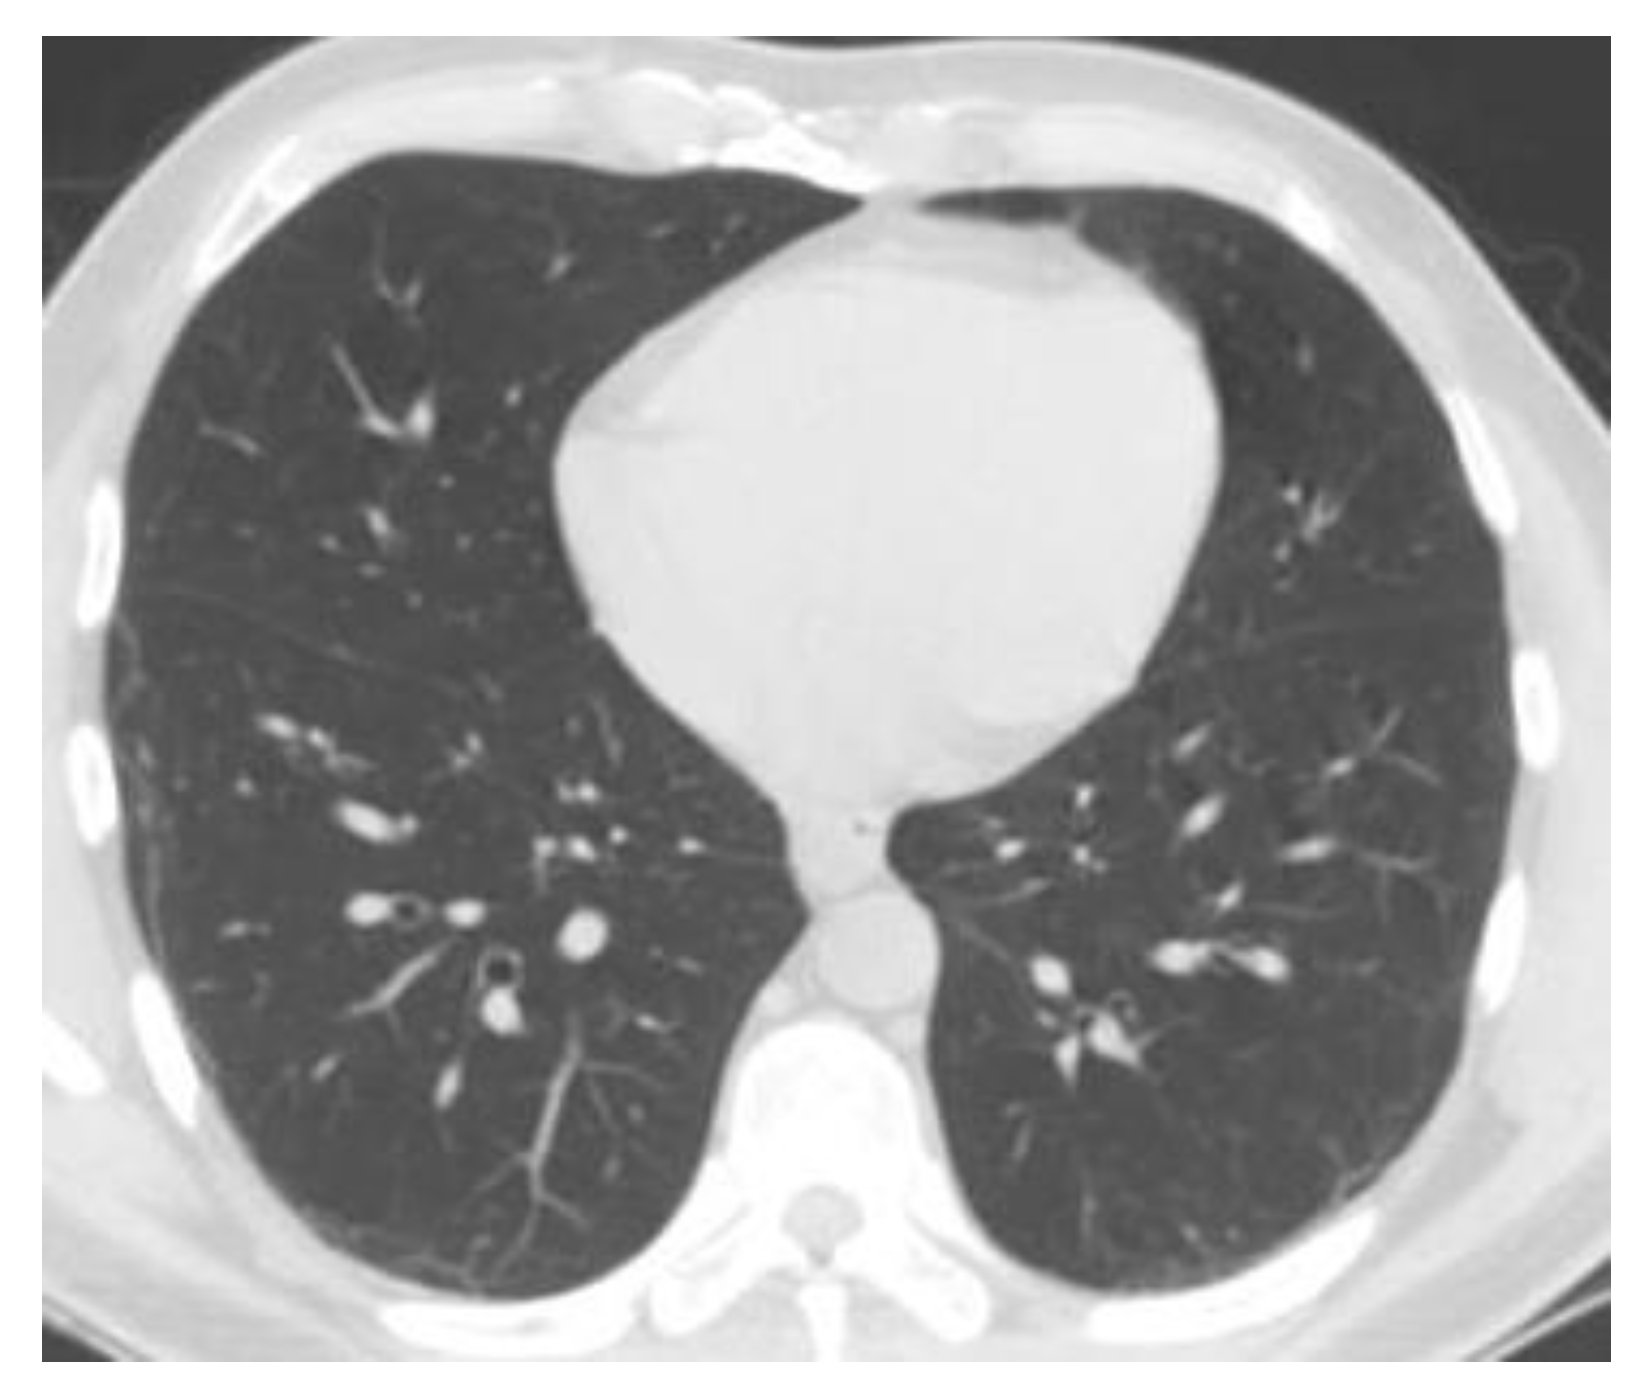

Figure 8 shows the complete module of some lung CT images affected by COVID-19 and images of lungs that did not suffer from COVID-19, unaffected by the virus, practically healthy lungs.

We mention that the set of images from Figure 8 and the license to use them can be found online at the address indicated in the bibliographic reference [21].

Figure 8. Image validation of the completed module.